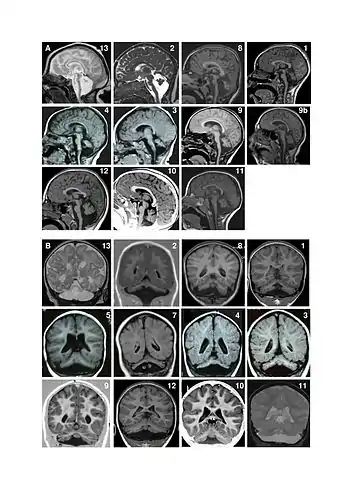

Pontocerebellar hypoplasia (PCH) is a heterogeneous group of rare neurodegenerative disorders caused by genetic mutations and characterised by progressive atrophy of various parts of the brain such as the cerebellum or brainstem (particularly the pons).[1] Where known, these disorders are inherited in an autosomal recessive fashion. There is no known cure for PCH.[2]

There are different signs and symptoms for different forms of pontocerebellar hypoplasia, at least six of which have been described by researchers. All forms involve abnormal development of the brain, leading to slow development, movement problems, and intellectual impairment.[2]

Classification

Pontocerebellar hypoplasia is classified as follows:[4]